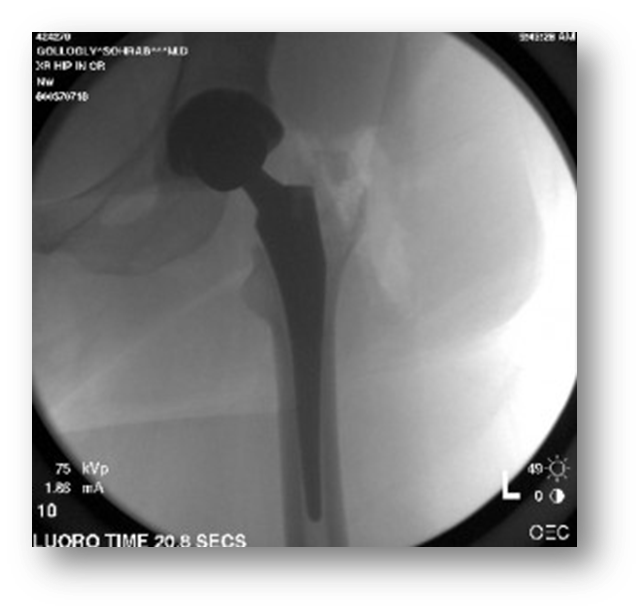

Hip nailing

Open reduction internal Fixation (ORIF) of a fractured proximal femur

An Orthopedic surgeon uses x-ray to guide the wire into the femur

The hardware might end up in the proximal femur (nailing) or extend down to the knee, rodding

Patient may be placed supine with legs crossed, supine with the unaffected leg frogged, or in a lateral position lying on the unaffected side

A bag is usually placed over the C-arm tube (bottom) due to the high level of vascularity of these cases

The C-Arm approaches from the unaffected side

sterile team on the affected side

Ensure Black Diamond video cord is plugged in and C-athe rm images are on the room monitor for the surgeon

C-arm responsibilities

Center and position the C-arm appropriately over patients affected hip

save images